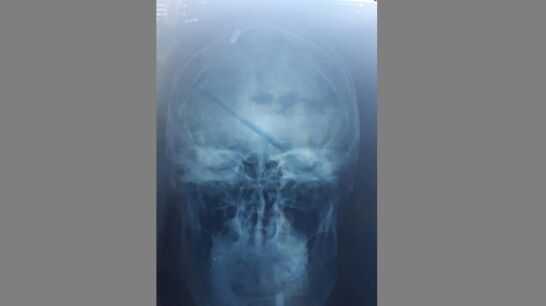

Harto de la situación, el joven decidió ir de nuevo al médico y, tras explicar lo que había pasado, decidieron hacerle una radiografía.

Cuando los médicos comprobaron lo que realmente había ocurrido, apenas podían creer lo que veían sus ojos. Leonardo Oyola tenía una bala alojada en el interior de su cabeza, el proyectil perdido había impactado casualmente en él.